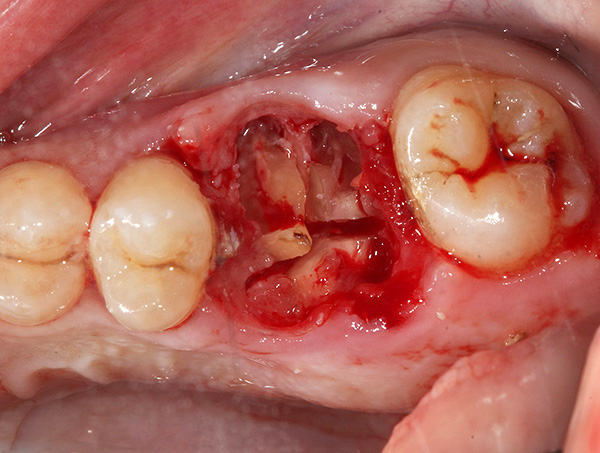

A fotografia abaixo mostra um exemplo de um dente serrado antes da remoção em três partes usando uma broca:

As fotos abaixo demonstram os estágios individuais do método atraumático de remoção de três dentes de uma só vez com um corte preliminar: